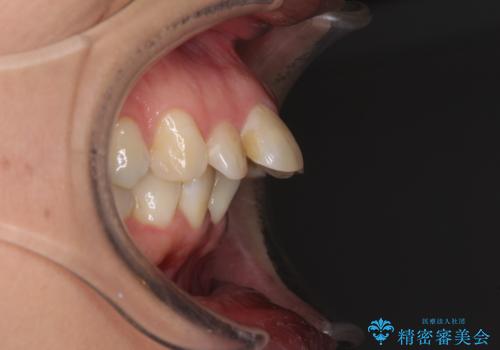

- 前歯のデコボコと前方に斜めに飛び出した前歯を気にして来院された患者様です。

口元の突出感はあまり気になっていませんでしたが、上下の前歯の前後差が大きかったため、上顎左右の第一小臼歯を抜歯し、上顎が裏側装置であるハーフリンガルにて矯正治療を行うこととしました。